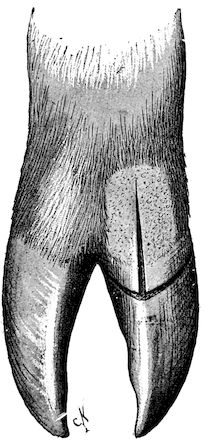

Fig. 10.—Dressing for fracture of the horn.

Symptoms. The symptoms are extremely simple. They consist mainly in the mobility of the fractured end, and such phenomena as sensitiveness, hæmorrhage, etc. When the fracture extends to the frontal bone, crepitation may also be noted.

Prognosis. The prognosis is not grave unless the fracture extends to the basilar half of the horn or affects the frontal bone.

Treatment. (1.) If the fracture is confined to the horn core, it is only necessary to bring the fragments into regular apposition, after having removed the broken end of the horn itself.

(2.) In treating a fracture affecting the middle portion of the horn or in treating animals destined for the butcher, the best method is to make a simple wound by dividing the parts with a saw below the fracture. This is a painful operation, necessitating anæsthesia, and requiring the animal to be cast or firmly fixed to a post or placed in a trevis. To diminish the painful stage of the operation, it was formerly recommended to make a circular incision extending through the entire thickness of the horn proper, and then to remove with a fine, very sharp saw the portion of the horn core. This, however, is scarcely practicable, and it is much better to make a direct section. Hæmorrhage is checked with compresses, moistened with cold water, after which a dressing known as the “Maltese cross dressing” (Fig. 10) is applied according to general principles.